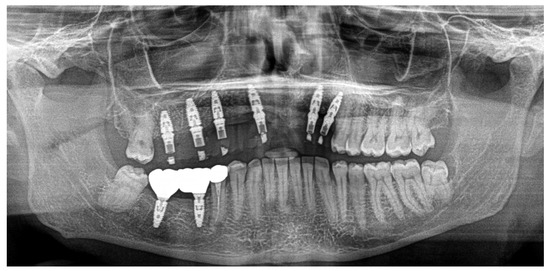

A 52-year-old patient, affected by non-Hodgkin lymphoma since March 2020 and treated with denosumab until June 2021, in clinical remission, presented in January 2022 for observation with multiple root resorptions, not of endodontic origin; it initially affected 22-21-11, but then, with rapid evolution, also affected 23-12-13-14-15-16-17-46-47, without referred pain. The resorption phenomena ended in September 2022. Since then, every radiographic check-up carried out to verify the progress of the regenerative bone surgeries has confirmed the arrest of the progression of the resorption phenomenon affecting the residual dental roots. In February 2022, as soon as responsibility for the patient’s care was assumed, in agreement with the oncology department of the hospital in Bergamo in which he was in care, given the severity of the lesions present (Figure 2), it was decided to extract the teeth (22-21-11), with a surgical toilet of the alveolus associated with decontamination with dye-free laser photodynamic therapy (February 2022).

Just two weeks later, a rapid worsening was observed (documented with periapical intraoral X-rays) of the elements (13-12-23), which led to their necessary extraction (May 2022), with decontamination of the alveoli, with the beginning of a reabsorption process involving 14-15-16-46-47 (March 2022) with delivery of a removable partial prosthesis (Figure 5).

60 days after the extraction of the upper front teeth, it was discovered that the upper right premolars were also affected by significant root resorption, as well as 46 and 47 (Figure 6).

Figure 2. Evolution of the external resorptions, with a rapid deterioration in only 2 weeks.

Figure 7. Ortopantomography (OPT) post-surgery in September 2023.